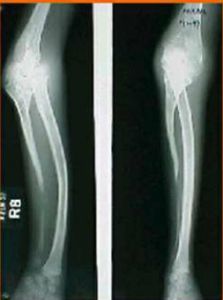

6、X射線:骨幹增粗密度大硬化不規則。骨腔變窄或消失、死骨形成等。

5、病理性骨折或脫位:骨皮質破壞致骨折、肌肉牽拉致脫位。